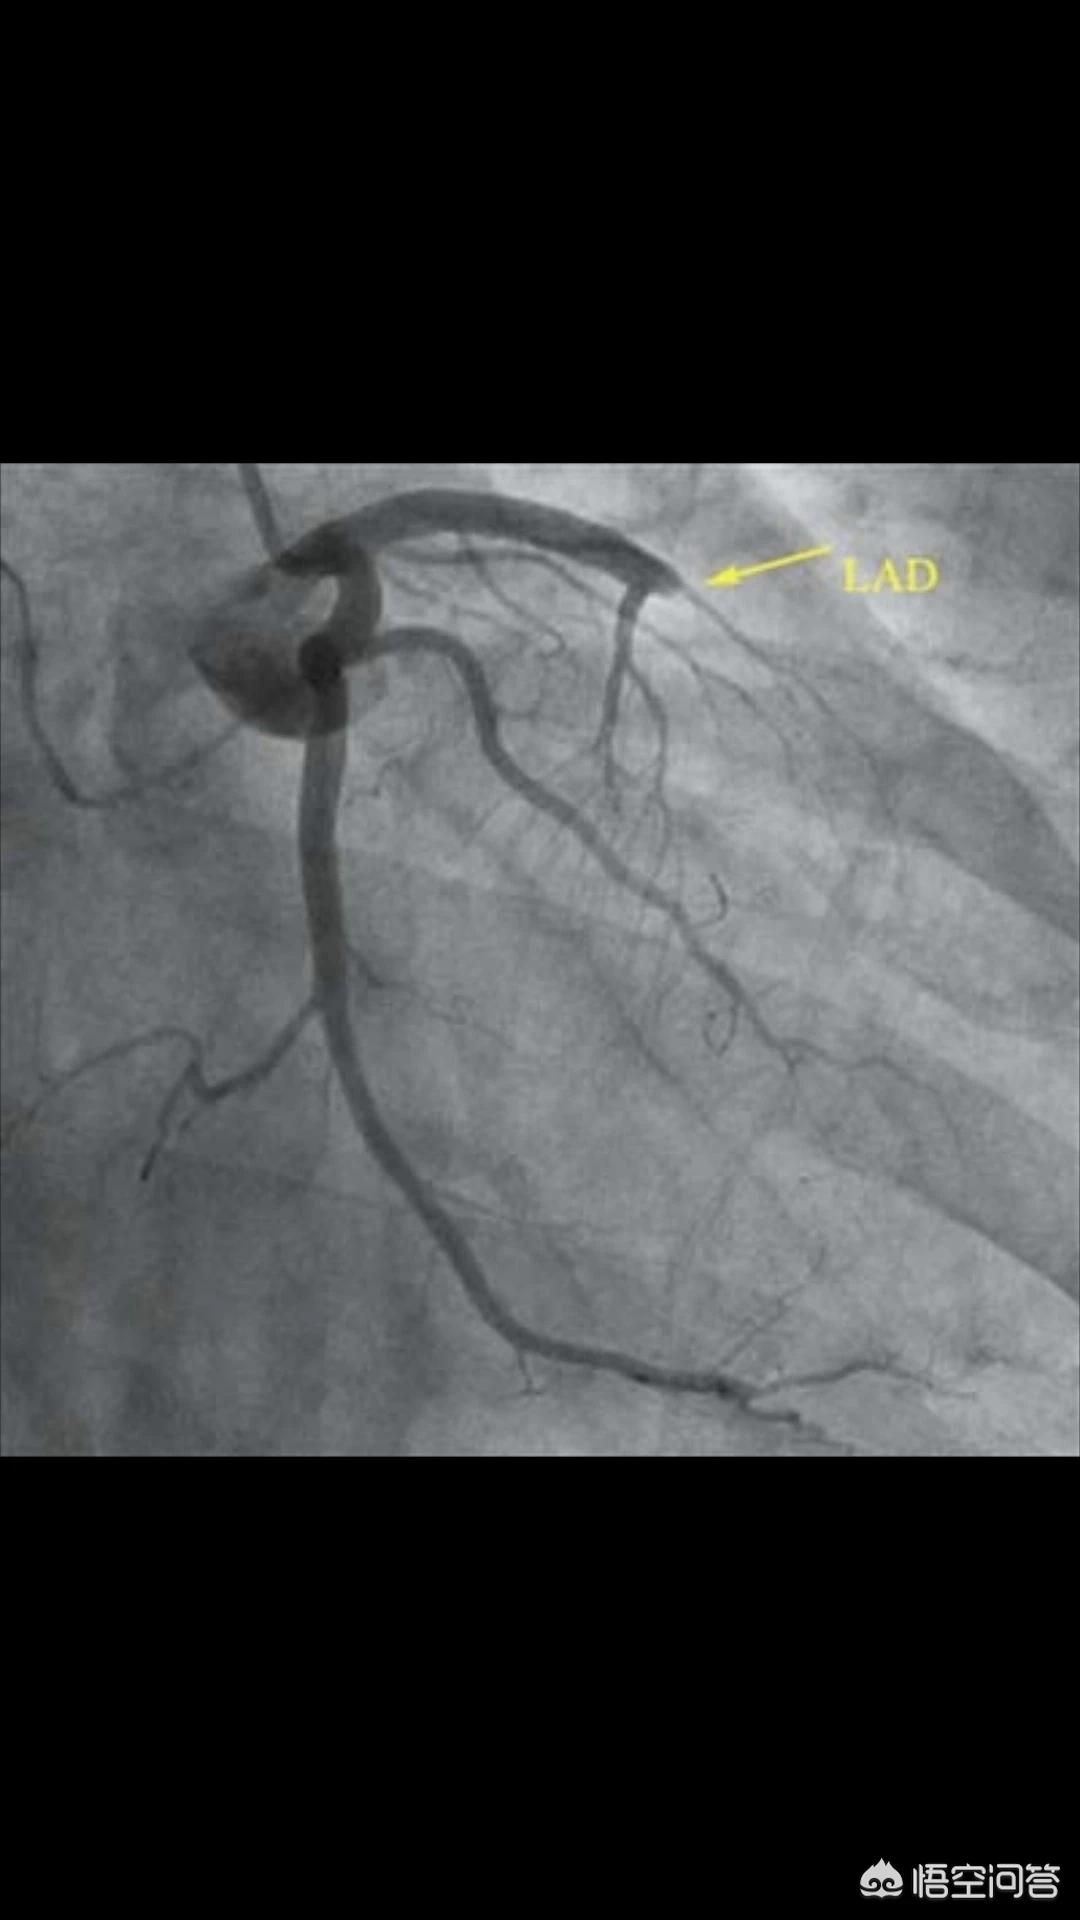

(前降支堵塞)